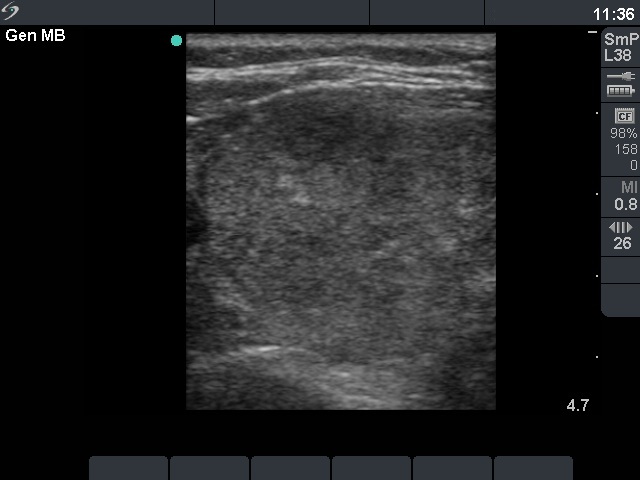

Ultrasonography: revealed a moderately hypoechogenic, inhomogeneous nodule in the left thyroid. The presence of a halo sign was equivocal, while the nodule displayed a type 2 vascular pattern.